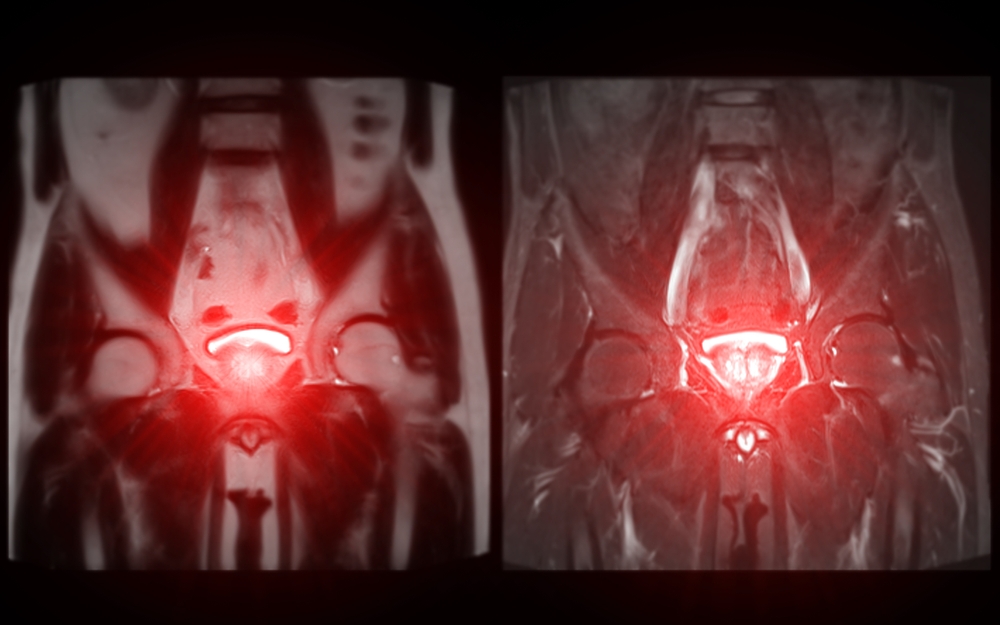

• Magnetinis rezonansas (MRT) – leidžia išsamiai įvertinti vidaus organus be rentgeno spindulių.